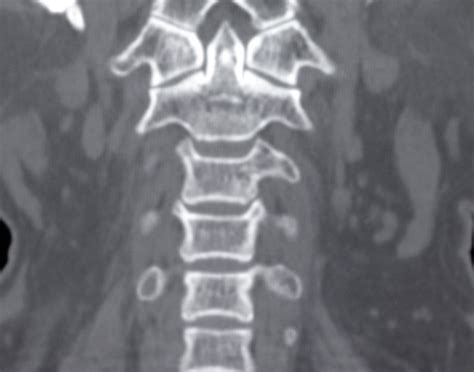

Cervical spine CT (Computed Tomography) scans use X-rays to create detailed images of the cervical spine. These images are particularly useful for identifying fractures, dislocations, and other structural abnormalities. Unlike traditional X-rays, CT scans provide cross-sectional views, offering a more comprehensive understanding of the spine's anatomy.

Interpreting cervical spine CT images requires a thorough understanding of spinal anatomy and the ability to identify various pathologies. Key structures to focus on include:

• The vertebrae, which are the individual bones that make up the spine.

• The intervertebral discs, which act as cushions between the vertebrae.

• The spinal canal, which houses the spinal cord.

• The facet joints, which allow for movement between the vertebrae.

Radiologists look for signs of fractures, dislocations, and other abnormalities that could indicate a spinal injury or condition. For example, a fracture may appear as a break in the continuity of the bone, while a dislocation may show misalignment of the vertebrae.

• Multiplanar Reconstruction (MPR): This technique allows for the creation of images in multiple planes (axial, sagittal, and coronal), providing a more comprehensive view of the spine.